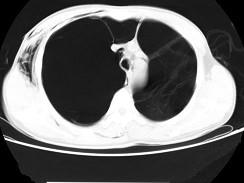

问题 男,32岁,被车撞伤后1小时,请结合影像图像选择其最可能的诊断为 ( )

选项 A、右侧肺大疱并皮下纵隔气肿 B、支气管断裂 C、右肺不张 D、右侧气胸并皮下纵隔气肿 E、右侧气胸

答案 D